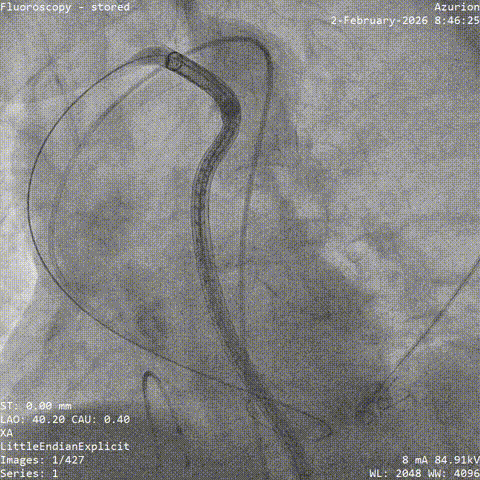

第一阶段,团队先为张老先生进行冠脉造影及介入治疗。结果显示,患者左前降支存在慢性完全闭塞病变,并伴有严重扭曲和钙化,常规处理难度较大。

在充分评估后,团队先对病变部位进行旋磨处理,再完成后续介入治疗。术后,张老先生病情稳定,未再出现心绞痛发作,也为后续主动脉瓣置换争取了更安全的条件。

▲冠脉造影:LAD-CTO病变,严重扭曲、钙化

▲开通,扭控MC

▲旋磨

▲术后